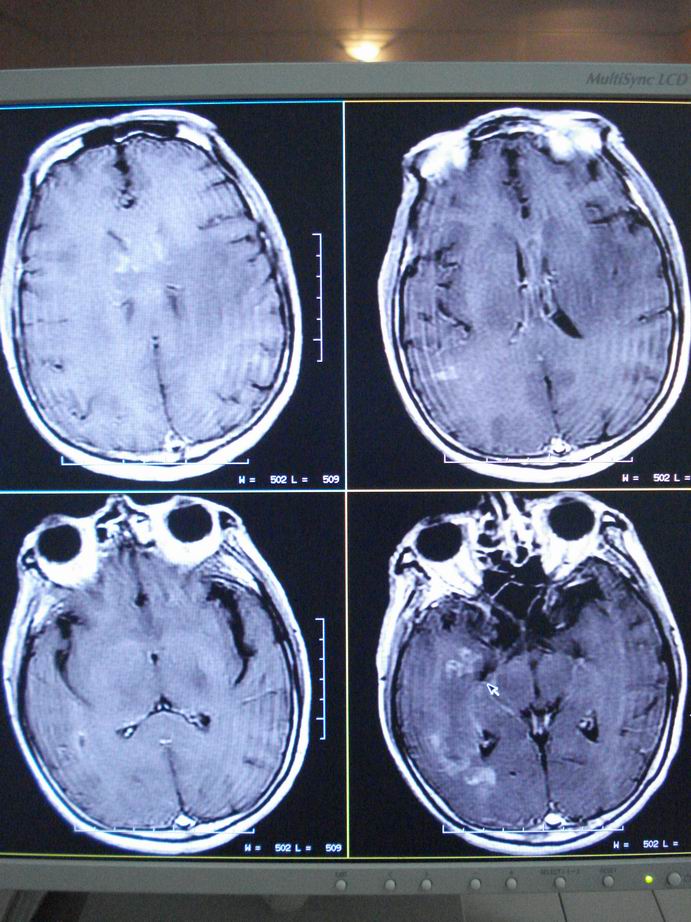

男60岁,左侧肢体乏力及精神异常10天,血压正常,血常规,肝肾功正常,腰穿无异常,请教颅内多发病灶,考虑什么?感染?肿瘤(转移性?)还是其它?

考虑为颅内多发转移瘤

脑内多发性转移瘤。

淋巴瘤较转移瘤可能大。

脑内多发占位性病变,首先考虑感染性病变,其次是转移瘤。

结合病人高龄,考虑转移瘤